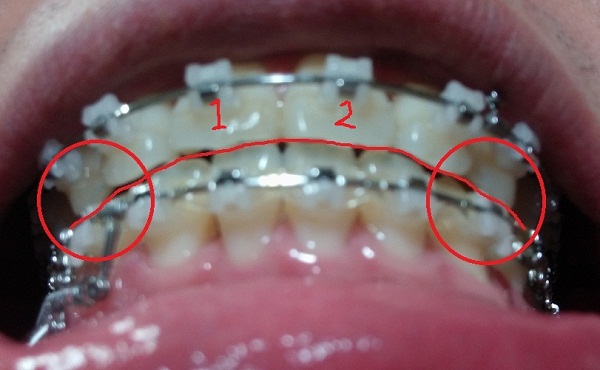

[정면]

[아래서 본 정면1]

[아래서본 정면2]

-중심선 99% 맞은 상태!!

-하악 파워체인으로 치아끼리 꽉 조여서 마무리로 가는 중!!

지금은 다행히 중심선도 다시 맞고 사진을 보시면 아시겠지만 교합이 거의 맞는 듯합니다.